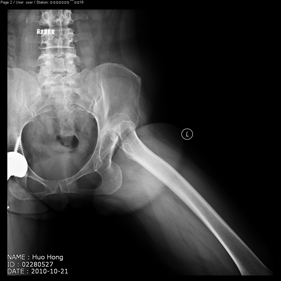

Department of Adult Joint Reconstructive Surgery

shortening osteotomy and total hip replacement for bilateral severe dysplasia of hip with high riding